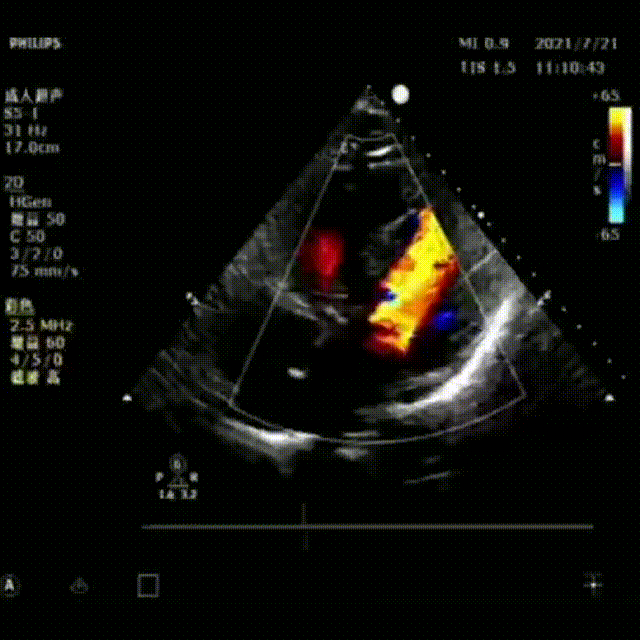

患者为75岁男性,胸闷憋气20余年。主动脉瓣重度狭窄伴重度反流,二尖瓣中度反流,合并冠心病,心律失常,二度房室传导阻滞,高血压,外周血管粥样硬化,心功能Ⅲ级。经术前超声心动图诊断,主动脉瓣前向血流速度4.3m/s,峰值压差74mmHg。

术后超声

术后几乎无压差,钙化一侧微量反流,瓣膜正常工作。